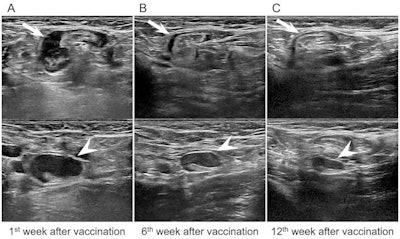

The team looked at data from 88 healthy women with COVID-19 vaccine-associated lymphadenopathy undergoing serial ultrasound. A total of 49 women underwent follow-up ultrasound at a median of 12 weeks, with a range of eight to 14 weeks.

After these women were vaccinated, persistent lymphadenopathy was observed in 25 women (51%). They found that complete resolution was observed at a median of six weeks, with a range of four to seven weeks, after vaccination in 23 women.